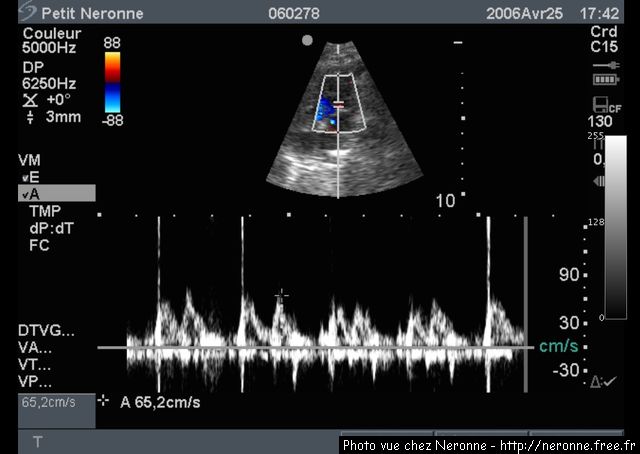

Il y a 2 ans ma vétérinaire avait détecté un petit souffle au coeur. En avril 2006 j'ai fait une échographie cardiaque qui a conclu que j'avais une discrète endocardiose mitrale (c'est à dire une petite fuite à la valve mitrale). Lundi dernier j'ai fait une nouvelle échographie qui a considéré que mon état était stationnaire.

Une image de l'échographie d'avril 2006